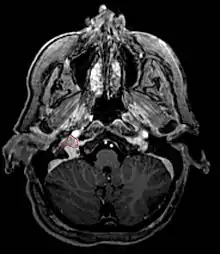

- Commonly arise from the paraganglia of the jugular bulb

- Typically invade the tympanic cavity and jugular foramen

- Can extensively invade petroclival region

- Can invade cavernous sinus above

- Can invade hypoglossal canal below

- Clinical presentation typically with tinnitus or hearing loss, but may also impact jugular foramen CNs